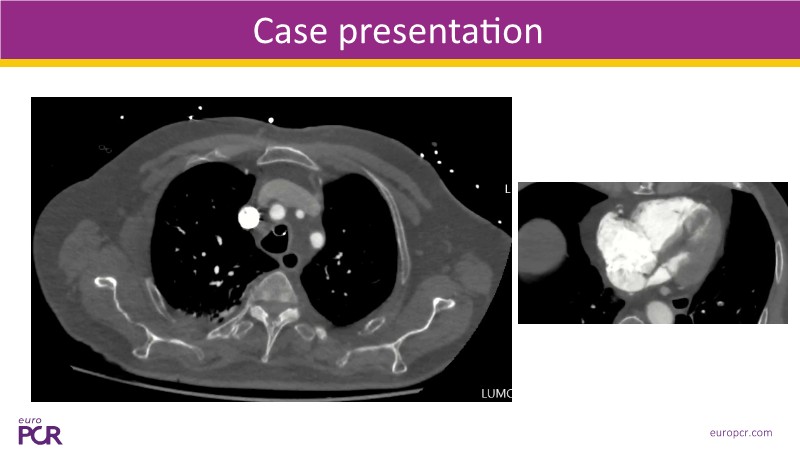

Watch this EuroPCR 2025 session on pulmonary embolism to explore the role of computer-assisted vacuum thrombectomy (CAVT) as an alternative to medical treatment in high-risk (massive) PE, supported by insights from the STRIKE PE study. Discover how CAVT rapidly and effectively offloads the right ventricle in intermediate-high-risk PE patients, especially those with a high bleeding risk. Review safety and efficacy data from a cohort of 450 patients demonstrating consistent procedural success. In short, this video provides a clear understanding of key procedural considerations, the latest evidence on Penumbra technology, and how ongoing innovation is shaping the future of PE management.